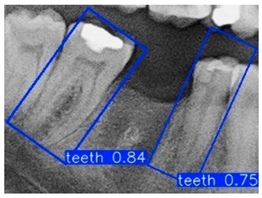

Further analysis revealed that although YOLOv11m performed slightly better on specific metrics, it was more prone to detection box shifts or overlaps in test images with complex backgrounds or blurred tooth boundaries, leading to reduced segmentation accuracy. As shown in Figure 10b, YOLOv11m produced detections with higher confidence scores; however, the predicted locations often deviated from the actual tooth positions. In contrast, Figure 10a illustrates that YOLOv9m, despite yielding slightly lower confidence scores, achieved superior localization accuracy with fewer false positives. This advantage was particularly evident in challenging cases involving blurred edges or narrow interdental spacing, where YOLOv9m consistently delivered stable predictions. The detection boxes generated by YOLOv9m provided higher accuracy and adhered more closely to the actual tooth contours, demonstrating greater stability and practical applicability. These strengths make YOLOv9m more suitable for subsequent fine-grained image segmentation and detailed dental structure analysis. Therefore, YOLOv9m was ultimately selected as the primary model for the following experiments, and all further applications and performance evaluations were conducted based on its outputs.

Figure 10.

Instance segmentation result comparison.